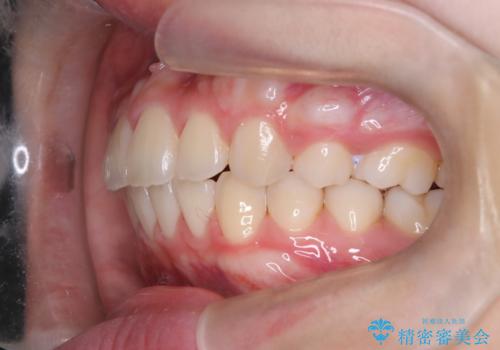

途中、矯正用のアンカースクリューを使うことで、最終的にきれいに前歯の真ん中を合わせることができました。

2年という矯正期間でしたが、かみ合わせも良くなりを患者様には満足していただくことができました。